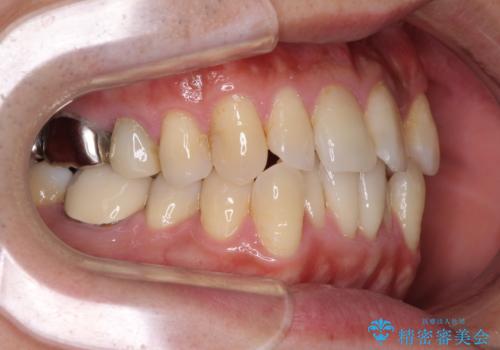

受け口傾向の咬み合わせ 前歯のデコボコをワイヤー矯正で素早く改善

前歯のクロスバイトは、改善の途中で歯髄壊死を起こすリスクが高くなるため、マウスピース矯正よりもワイヤー矯正をお勧めしております。

この患者様もクロスバイトはあっという間に改善され、1年強で速やかに治療を終えることができました。